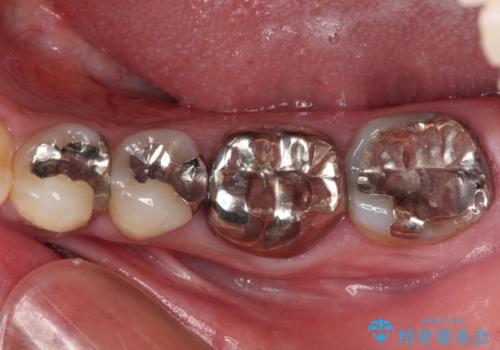

- 根っこの一部だけになった歯と咬むと痛みのある歯を気にして来院された患者様です。

上顎の歯根のみとなった歯は抜歯が必要であったので、抜歯を行い、インプラントあるいはブリッジのよる補綴治療を提案しました。

前後の歯は銀歯が装着されていたため、ブリッジによる補綴治療として、前後の歯もセラミックに置き換えることとしました。

下顎の根管治療がされた大臼歯は咬合時に痛みが認められたため、再度根管治療を行った後に補綴治療することとしました。